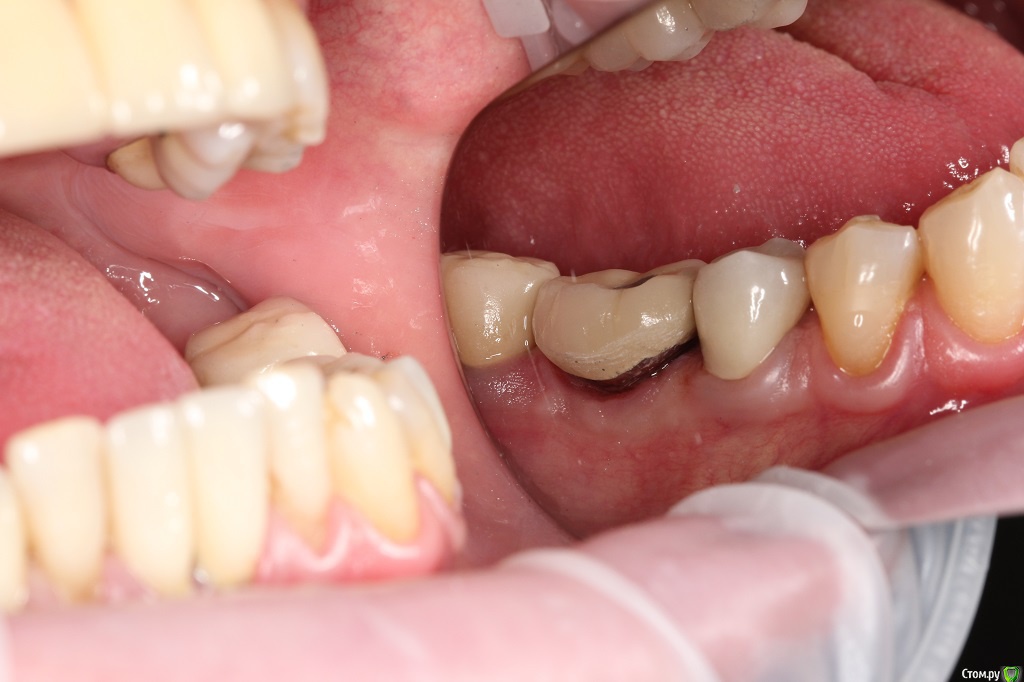

Dr.Sham Опубликовано 11 марта, 2015 Поделиться Опубликовано 11 марта, 2015 (изменено) Год назад в другой клиник пациенту устанавливали имплантаты, вроде одномоментно с удалением.На сегодняшний день жалобы стандартные для такой ситуации (пища застревает, запах изо рта).Коронки демонтировал, увидел "козырьки", нехватку десны, отсутсвие 3 мм от профиля прорезывния до платформы.По КТ, стандартно для селекта - отсутсвие 1,5-2 мм кости по кругу, в полости рта признаков воспаления я не диагностирую, отделяемого нет. На данный момент просто выполировал шейки, чтобы не было козырьков, но пища застревает еще больше, насколько я понимаю. В области 36 - язычно норм, вестибулярно - всего 1 мм, расщепить лоскут вестибулярно и подсадить трансплантат с неба, получим ширину, но не высоту, но как без козырька размоделировать коронку?В области 45 - вестибулярно высота есть, а язычно всего 1 мм, расеплять язычно ищечно и добавлять десну?Если так, то на фдмках вести или как?В области 46 - высота есть по кругу, но нет ЗКПД, какой метод предпочесть, чтобы сохранить уже имеющуюся БШ?Как выходить из ситуации?Кто что думает. Спасибо.Теоретически можно вынуть болты, но интегрированный нобель пару раз выкручивал - выпиливал, удовольствие сомнительное.ПС кстати обратите внимание на цемент на границе коронка-абатмент! Изменено 11 марта, 2015 пользователем Dr.Sham Ссылка на комментарий